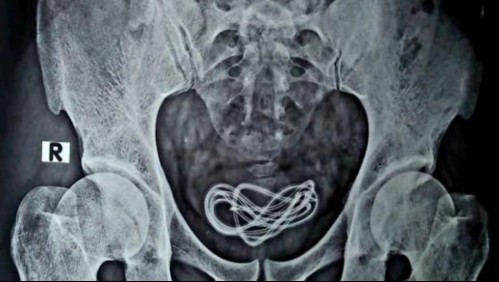

Mundo Le extrajeron el cable de un cargador de celular de 60 centímetros de la vejiga: Lo usó como juguete sexual